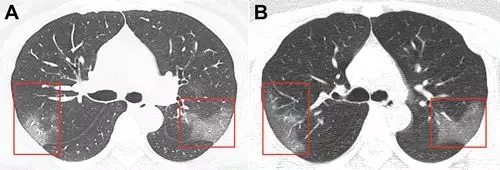

肺部CT扫描(见下图A)

两侧肺上叶肺段呈斑片状毛玻璃样显影。

3天后,再次CT检查发现,

两肺的毛玻璃显影更大了(图片B),

显示治疗效果不好,病情加重。